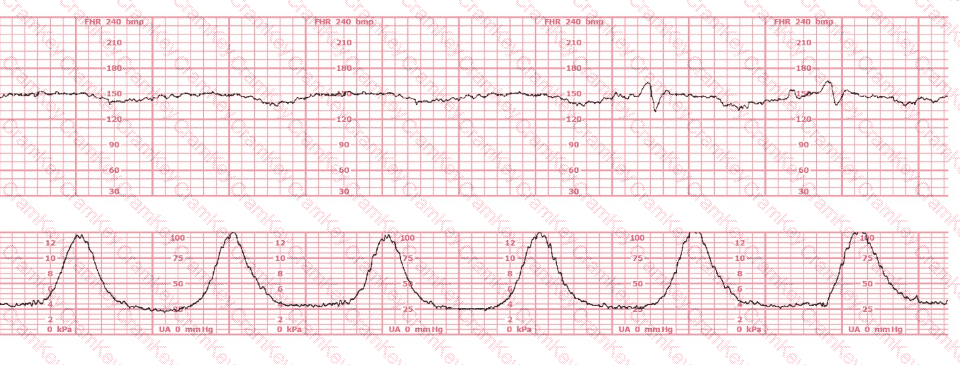

This patient received an epidural 15 minutes prior to the tracing shown. The next course of action is to:

Questions 8

Options:

A.

Check maternal blood pressure

B.

Continue to monitor

C.

Perform a cervical exam

Discussion